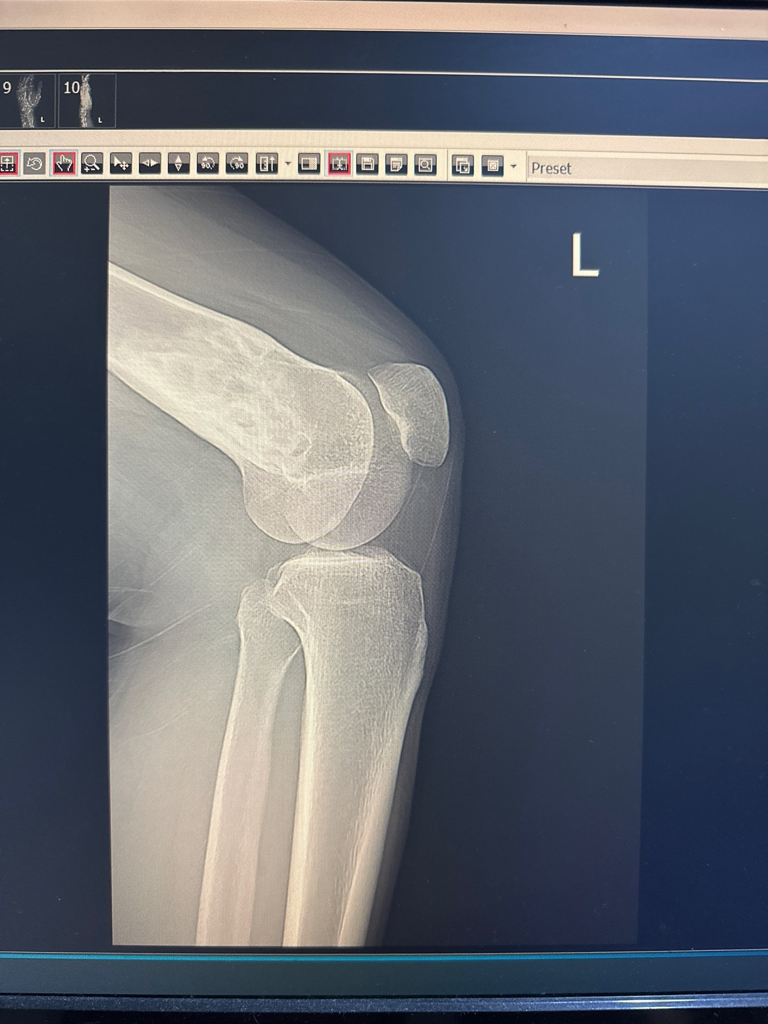

엑스레이 사진만으로는 평가가 제한됩니다. 이상 소견이 있는 것으로 보이는데 그것이 뼈 내부에 종양이 있는 것인지 아니면 다른 문제가 있는 것인지 등 구체적으로 감별이 어렵습니다. MRI 등 정밀 검사를 진행해보는 것이 필요해 보입니다.

지금 엑스레이만 봐서는 정확하게 알기 어렵지만 뼈에 종양이 발생하였을 가능성도 있습니다. 이를 정확하게 진단하기 위해서는 CT나 MRI를 촬영해 볼 필요가 있습니다.

안녕하세요. 영상의학과 전문의 최원제 의사입니다.

비골화성 섬유종 등 골종양의 소견이 의심됩니다.

MRI를 찍어보셔서 정확한 진단을 받아보시는 걸 추천드립니다.